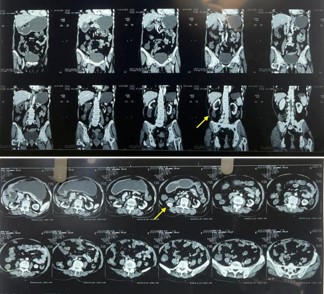

Investigations: Ultrasonography of the abdomen showed a 1.6 cm fascial defect in the posterior abdominal wall with herniation of omental fat, and a 1.3×2.9 cm hypoechoic lesion in the right lumbar region. Contrast-enhanced CT confirmed a 1.4 cm defect in the right superior lumbar triangle with a hernial sac measuring 6.5×2.4×8.3 cm extending from T11 to L2, containing omental fat (Figure 2). Notably, no bowel loops were involved. Additional findings included gallbladder sludge and benign renal cysts. Routine hematological and biochemical investigations were within normal limits. Preoperative cardiac evaluation revealed mild cardiomegaly with a small pericardial effusion but preserved function.

Figure 2: (A) CT scan showing the location of the defect (coronal section). (B) CT scan showing the location of the defect (axial section).